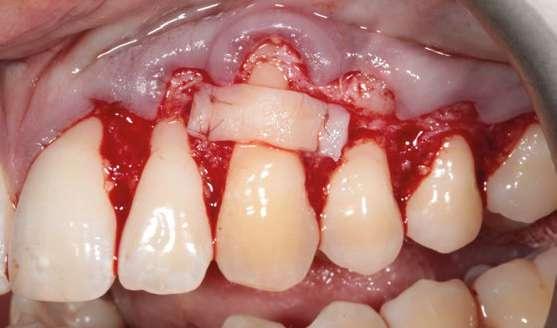

Después de un detallado análisis y valoración de las alternativas terapéuticas, se planificaron 2 procedimientos quirúrgicos mediante colgajos de avance coronal con acceso lateral y sin descargas para el tratamiento de las recesiones del maxilar superior (Fig. 2) (7-9).

A continuación procederemos a describir el paso a paso del tratamiento quirúrgico de las recesiones (Figs. 2 a 7). Ambos procedimientos quirúrgicos se realizaron bajo anestesia local y sedación consciente por vía endovenosa y con un tiempo de descanso para el paciente entre procedimientos de 1 mes y medio. En este caso, el eje de rotación fueron los caninos en ambos lados y todas las incisiones para-marginales oblicuas (líneas punteadas en rojo) se realizaron hacia estos dientes (Fig. 2).

Figura 2. Planificación quirúrgica.

Figura 4. Diseño de las incisiones y del colgajo. Nótese la creación de una “falsa recesión” en

colgajo al finalizar el avance coronal.

Figura 3. Situación clínica el día de la intervención quirúrgica.